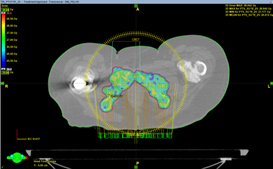

Пациентка N обратилась в клинику с жалобами на сильные боли в области седалищных костей, частично купирующиеся на фоне приема Трамадола. В связи с невозможностью опоры на левую нижнюю конечность (перелом шейки бедренной кости; в анамнезе остеосинтез по поводу перелома шейки правой бедренной кости) вынуждена большую часть времени находиться в сидячем положении, что в свою очередь усиливает болевой синдром.

При контрольных обследованиях выявлено метастатическое поражение лонных и седалищных костей с обеих сторон, больших размеров, с образованием обширных дефектов в костной ткани, с вовлечением мягких тканей и реактивным воспалением.

В связи с анатомической особенностью локализации метастатического процесса и размеров очагов с целью купирования болевого синдрома пациентке рекомендовано проведение паллиативного курса дистанционной лучевой терапии на область метастатических очагов в лонных и седалищных костях с обеих сторон в разовой дозе 5 Гр за 5 фракций (до суммарной дозы 25 Гр).

курс дистанционной лучевой терапии курс дистанционной лучевой терапии